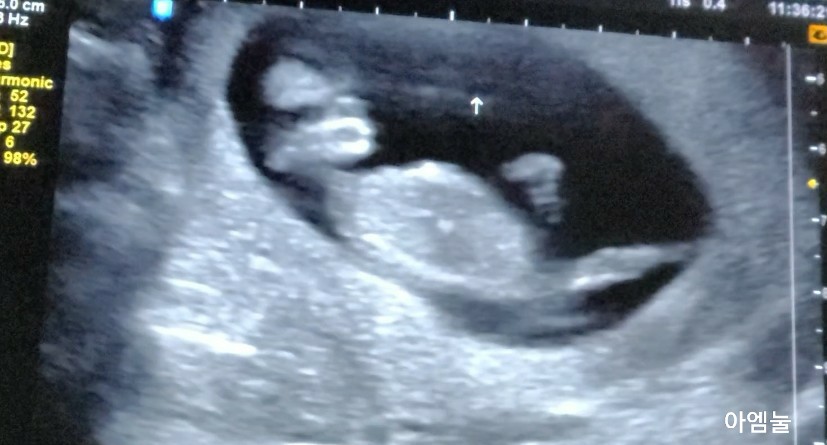

동영상 촬영 가능한지 물어보고 8주차부터는 찍어보세요. 2주만에 크게 성장한 봄이! 어디가 어딘지 박 선생님이 말하지 않아도 다 알게 되었습니다.(다음에 주수별로 올릴게요)

태아가 움직이지 않아서 배를 톡톡 만지거나 초코우유를 미리 먹는다는데 저는 정말 다행히 범이가 많이 움직여 주었습니다.ㅋㅋㅋㅋㅋㅋㅋㅋㅋㅋㅋㅋㅋㅋㅋㅋㅋㅋ 선생님이 얘 난리라고, 웃겼어요)